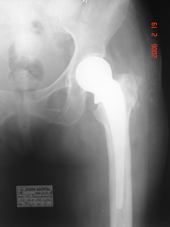

| Fracture neck of femur pre op |

Fracture neck of femur post op |